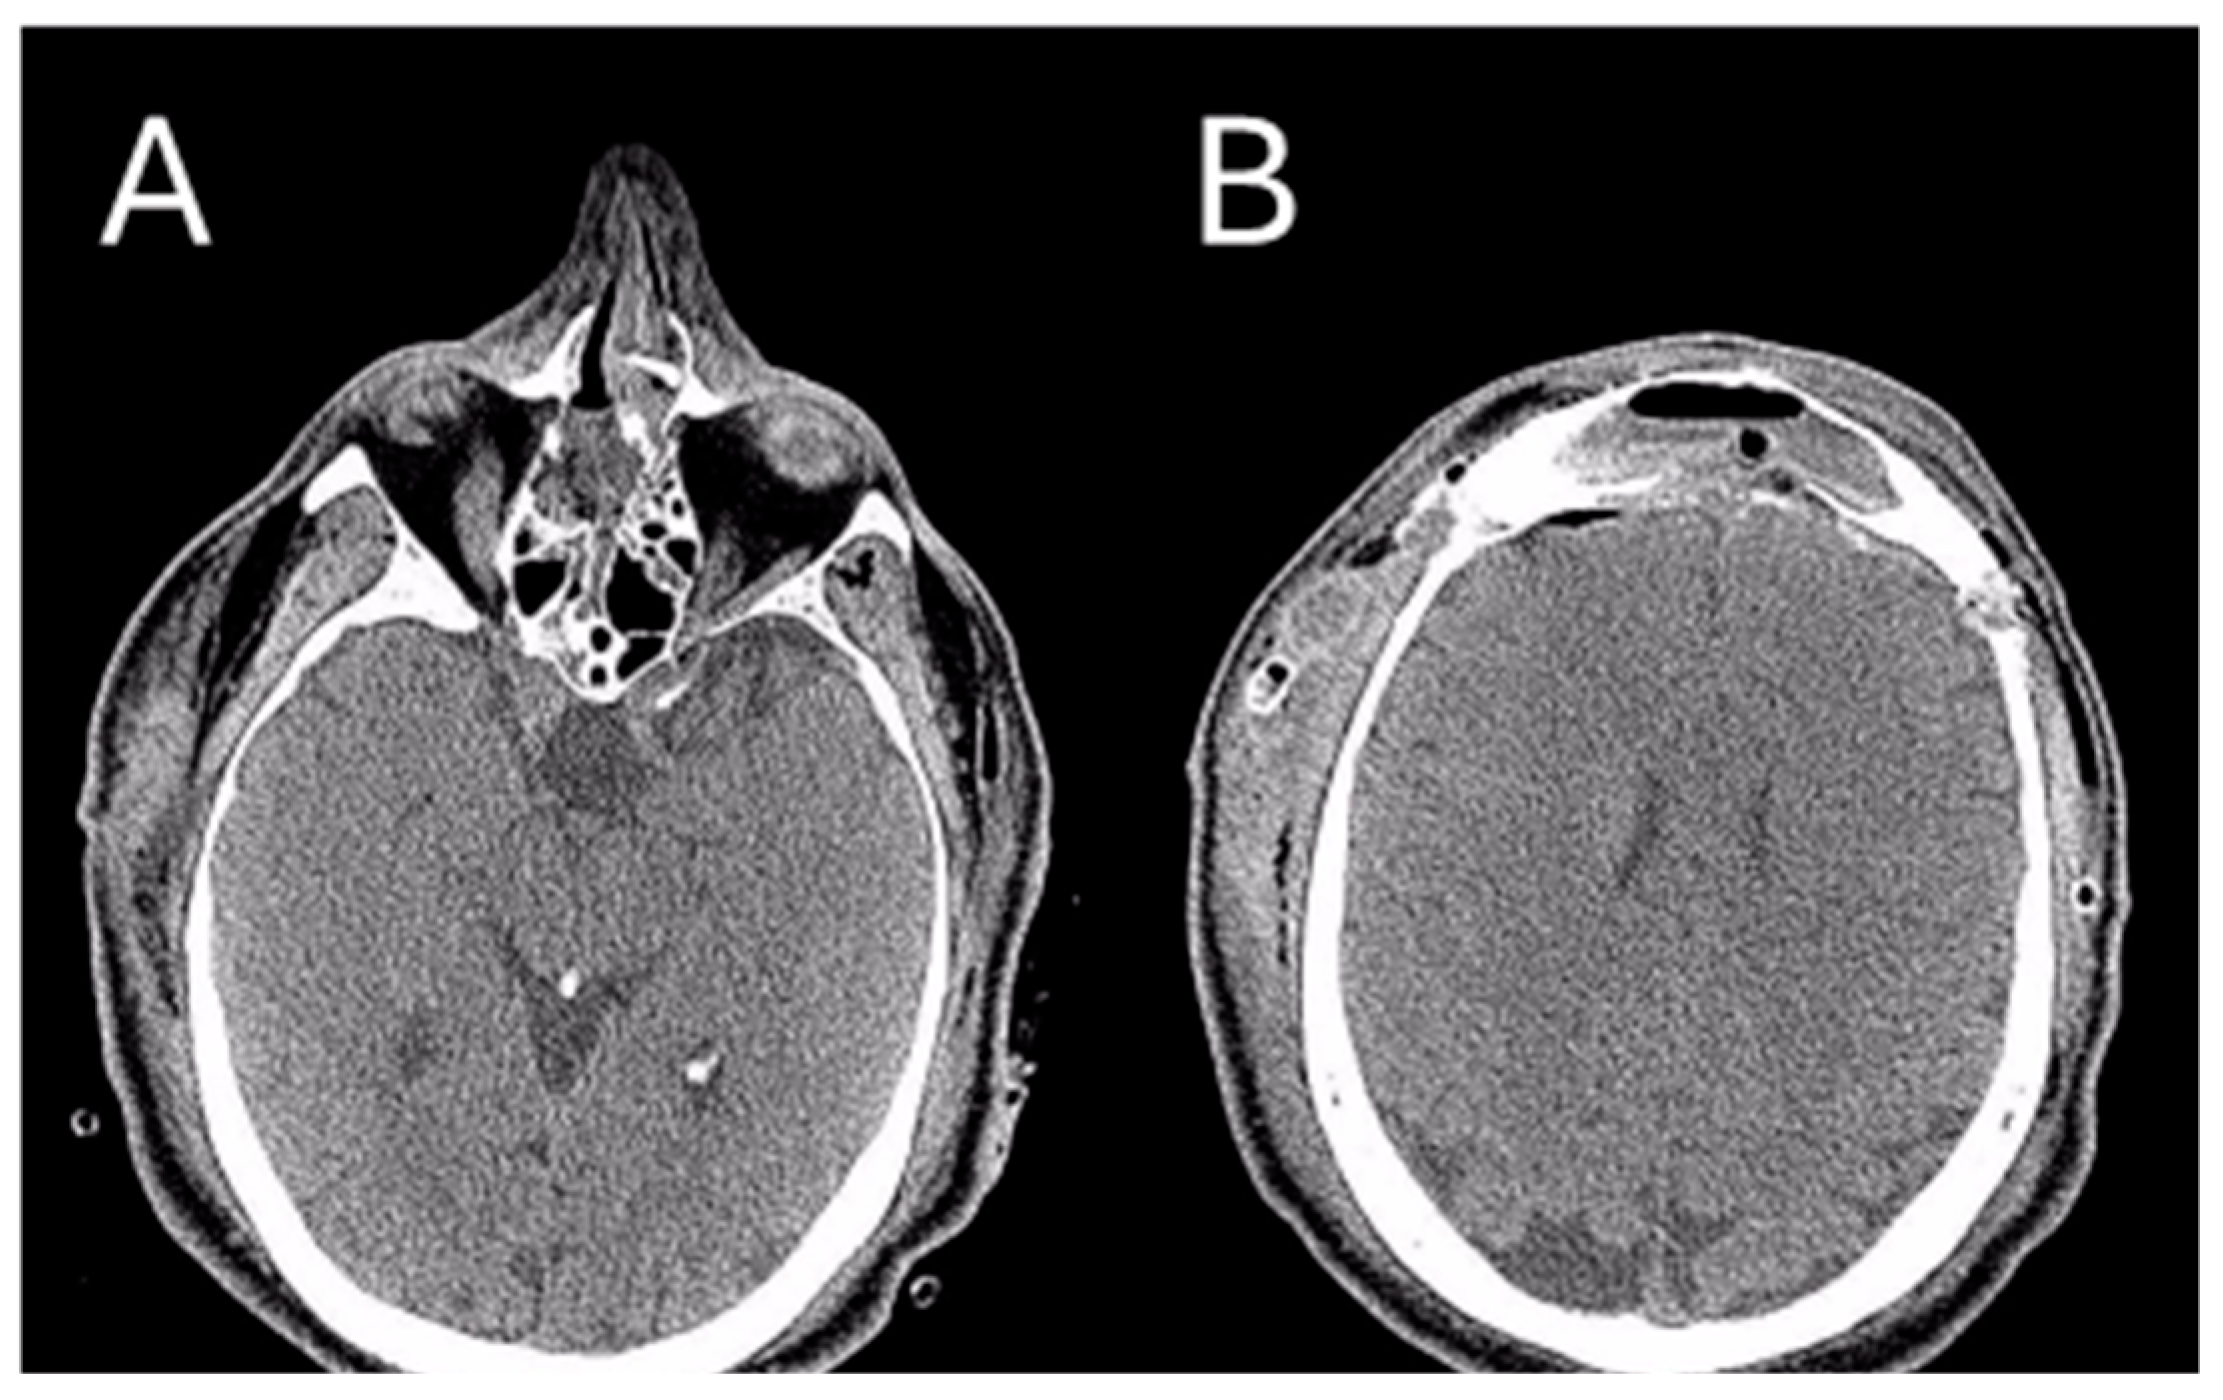

After the surgical intervention, a skull CT scan was performed, revealing a near-complete removal of the lesion (Figure 6).

Figure 6.

Post-operative CT image of Patient 2. Two axial cuts of the post-operative CT scan are appreciatedat the same level as those shown in Figure 3 to demonstrate the outcomes of the surgical removal. (A) the absence of the lesion localized at the ethmoidal level (B) The absence of the lesion localized in the right frontal sinus.